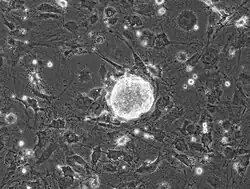

As the continued research and application of ESCs and iPSCs expands in regenerative medicine models, quality checks of test cells are needed. A widely accepted procedure that works for both mammalian ESCs and iPSCs is the teratoma formation assay.[26] A teratoma is a benign(typically) tumor that is characterized by its ability to form the three germ layers: ectoderm (nerves, epithelium), mesoderm (muscle, bone, and cartilage), and endoderm (gut).[26]

A teratoma formation assay is done by injecting test cells that are expected pluripotent cells into various tissues. A few areas include but are not limited to: the kidney capsule, intra-testicular, and intramuscular regions of mice that are immune-deficient.[26][27] Determined pluripotency is characterized by the test cell's ability to form a teratoma that is capable of producing the three distinct germ layers.

While the teratoma formation assay is considered the "gold standard" among researchers, many issues have arisen with the test.[26] One particular issue is the lack of standardization regarding specific details and factors that influence teratoma formation. Areas of concern for standardization are graft sites, age of test organism (typically mice), and the number of cells being injected into the test organism. These assays are also costly and operationally burdensome, and ethical concerns are an issue due to the use of test organisms.[26]

Another issue with this type of testing is the possibility of histological reading errors. Cells that are not completely reprogrammed into iPSCs that form noticeable cell masses, which look similar characteristically to teratomas, may be judged as pluripotent while lacking the three germ layers. The need for tracking of cell lineages and host versus donor cell markings has also been noted. Certain cell preparation materials may induce an inflammatory response or a foreign antigen immune response. These responses may play a role in falsely identifying differentiation of the test cells.[26]